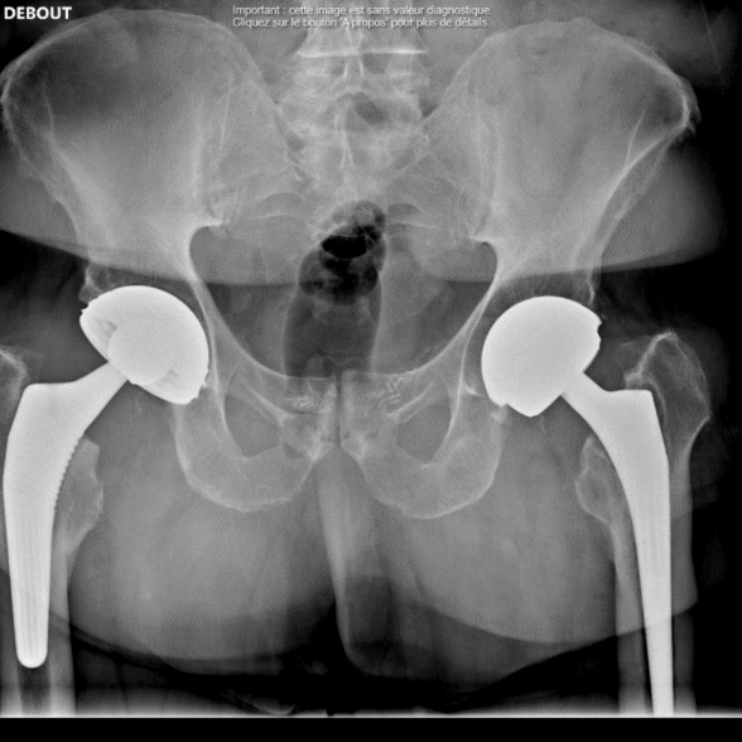

Une attention particulière est portée à la chirurgie mini-invasive, dont l’arthroscopie de la hanche, la prothèse de hanche par voie antérieure, l’arthroscopie du genou, l’arthroscopie de l’épaule et la chirurgie percutanée.

En combinant savoir-faire chirurgical et technologies innovantes, le Dr Majed Issa intervient sur de nombreuses pathologies articulaires. Que ce soit pour une arthroscopie de la hanche, une prothèse de genou personnalisée, ou encore une intervention sur l’épaule, le pied, la cheville, la main ou le poignet, nous mettons en œuvre des techniques précises et adaptées à chaque patient.